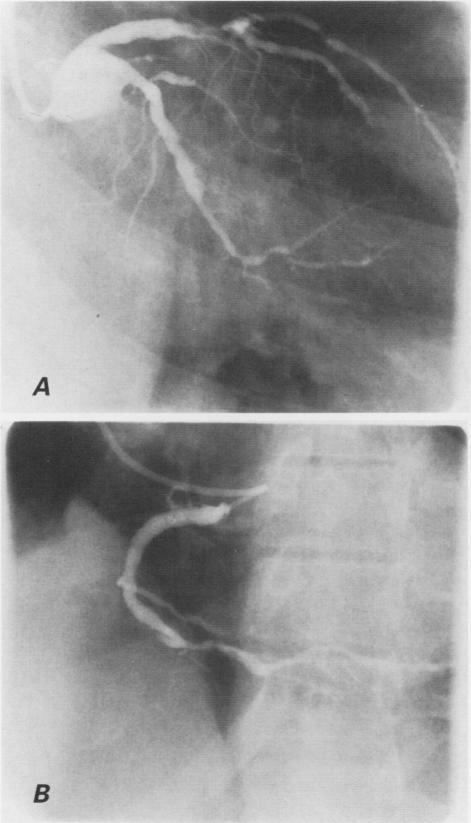

埃及冠心病患者的冠状动脉扩张

Coronary artery ectasia in Egyptian patients with coronary artery disease.

We conducted a retrospective study of 45 Egyptian patients with coronary artery ectasia who underwent coronary bypass grafting at our institution between 1980 and 1995. We examined the anatomic distribution and type of coronary ectasia and its association with coronary risk factors in these patients, and evaluated the severity of their coronary artery disease. We compared these findings with those from a group of 230 Egyptian patients who did not have coronary ectasia. These patients also underwent coronary artery bypass grafting between 1980 and 1995 at our institution. Obesity was present in 60% of the patients who had coronary artery ectasia, compared with 42% of patients who did not have ectasia (P < 0.01). Coronary artery ectasia was not related to any coronary risk factors other than obesity. However, patients who had ectasia did have a higher rate of triple-vessel coronary artery disease than did patients without ectasia (82% vs 67%, P < 0.05). Of the coronary vessels affected by ectasia, 43% were left anterior descending arteries. Diffuse disease was noted in 84% of all ectatic segments. We conclude that in this patient population, 2 conditions had a positive correlation with coronary ectasia: obesity and the severity of coronary artery disease.

我们对1980年至1995年间在我院接受冠状动脉旁路移植术的45例埃及冠状动脉扩张患者进行了一项回顾性研究。我们检查了这些患者冠状动脉扩张的解剖分布、类型及其与冠状动脉危险因素的关联,并评估了他们冠状动脉疾病的严重程度。我们将这些结果与一组230例无冠状动脉扩张的埃及患者的结果进行了比较。这些患者也于1980年至1995年间在我院接受了冠状动脉旁路移植术。60%有冠状动脉扩张的患者存在肥胖,而无扩张的患者中这一比例为42%(P<0.01)。除肥胖外,冠状动脉扩张与任何冠状动脉危险因素均无关联。然而,有扩张的患者三支血管冠状动脉疾病的发生率高于无扩张的患者(82%对67%,P<0.05)。在受扩张影响的冠状动脉血管中,43%为左前降支动脉。在所有扩张节段中,84%发现有弥漫性病变。我们得出结论,在这一患者群体中,有两种情况与冠状动脉扩张呈正相关:肥胖和冠状动脉疾病的严重程度。